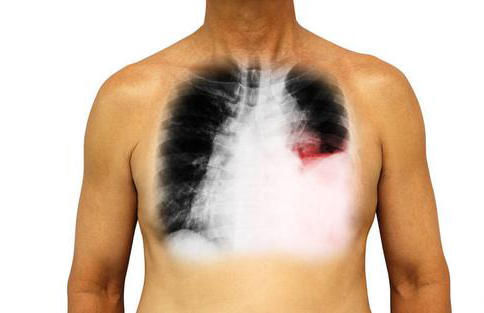

肺部疾病症状很多,大部分局限在肺,比如咳嗽、咳痰,气喘、胸闷,唯独肺癌与其他肺病不同,即使没有发生转移,也可能在肺以外部位出现症状,甚至发生在咳嗽、咳痰这些症状之前,如果能尽早想到肺部并及时诊治,可能延长生命,提高生活质量,减轻痛苦,如果肺癌还在早期,甚至可以手术根治。下面我们来看看都有哪些这样的表现。

单侧上肢或者胸部潮红出汗

这种现象很多人会有,但大部分表现为左右交替出现,侧卧时靠上的一边容易出汗,但某些肺癌患者则表现为固定的一边出汗,上肢、胸部单独或者同时出现出汗及潮红现象,严重时会蔓延到面部,甚至会引起一侧眼皮下垂,瞳孔缩小,两只眼睛不一样大,这种肺癌大部分发生于肺尖部位,在肺的最上面,拍胸片容易遗漏,必要时做个CT,一目了然。